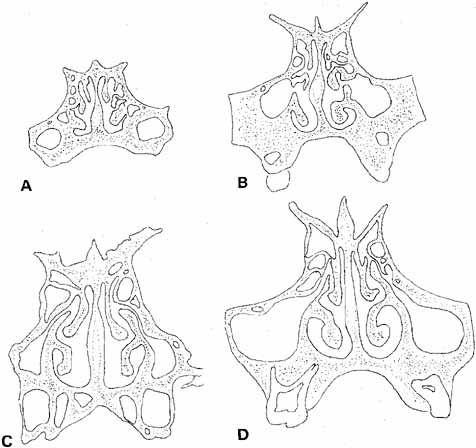

of the nose, the lateral nasal wall, and the inferior turbinate (Fig. 22).73 Silastic intubation of the nasolacrimal duct can be particularly traumatic

if the probes are not malleable (Fig. 23). By the age of 3 years, more space has developed, but it is still

less than half of that present in the adult. For this reason, it can

be difficult to reach in and withdraw the probe with Silastic tubing

from the inferior of the nose without causing trauma to the nasolacrimal

duct in the interior of the nose. Enlarging this space by using a nasal

facilitates visualization and removal of the probe.  Fig. 22 Coronal sections through the nasal fossa and sinuses showing their sizes

and relationships through various ages. A. Age 5 weeks. B. Age 3½ years. C. Age 7 years. D. Age 9 years. (Bernstein L: Pediatric sinus problems. Otolaryngol

Clin North Am 4:128, 1971) Fig. 22 Coronal sections through the nasal fossa and sinuses showing their sizes

and relationships through various ages. A. Age 5 weeks. B. Age 3½ years. C. Age 7 years. D. Age 9 years. (Bernstein L: Pediatric sinus problems. Otolaryngol

Clin North Am 4:128, 1971)